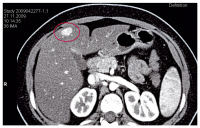

CT des Oberbauchs mit Kontrastmittel

Abbildung 2: CT des Oberbauchs mit Kontrastmittel: In der portalvenösen Phase homogene Kontrastmittelanfärbung eines Pelioseherdes im Lebersegment 2. Ein weiterer, kleiner, homogen angefärbter Herd zeigt sich am Unterrand der Leber.

Keywords: CThomogene KontrastmittelanfärbungKontrastmittelLebersegment 2OberbauchPelioseherdportalvenöse Phase

Abbildung 3: CT des Oberbauchs mit Kontrastmittel: In der portalvenösen Phase homogene Kontrastmittelanfärbung eines Pelioseherdes im Lebersegment 4b.

Keywords: CThomogene KontrastmittelfärbungKontrastmittelLebersegment 4bOberbauchPelioseherdportalvenöse Phase